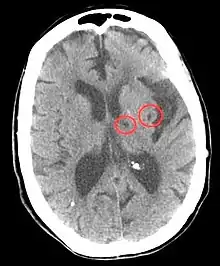

Hypertension is the leading cause of strokes and studies show that it increases the risk of a stroke by 220%[17][18] and stroke is the leading cause of long-term disability.[19] High blood pressure weakens arteries (small vessel disease) and causes blood vessels to be more likely to clog and/or burst. A lacunar infarction occurs when an artery is blocked and an intracerebral hemorrhage occurs when the blood vessels burst. In turn, the brain is more vulnerable to ischemic insults as there is a dysregulation in the supply of blood and oxygen.[19] More specifically, hypertension inflicts damage to small resistance arteries, which supply nutrients to the internal capsule, brainstem, thalamus, cerebellum, and basal ganglia, and cause cell death and tissue degeneration.[3] Blood clots also accelerate arterioscelerosis, which causes arteries to thicken and harden.[20] Essentially, hypertension is the biggest risk factor for stroke and tissue damage caused by a stroke is a major risk factor for cognitive decline, therefore the risk of stroke may act as a mediator in the relationship between blood pressure and cognition.[21] Besides lifestyle modifications, blood pressure control is the #1 treatment for stroke prevention. Antihypertensive medication show a protective effect against stroke-related cognitive impairments.[3]

Hypertension→ Small vessel disease → Lacunar infarction & Intracerebral hemorrhage → Tissue damage